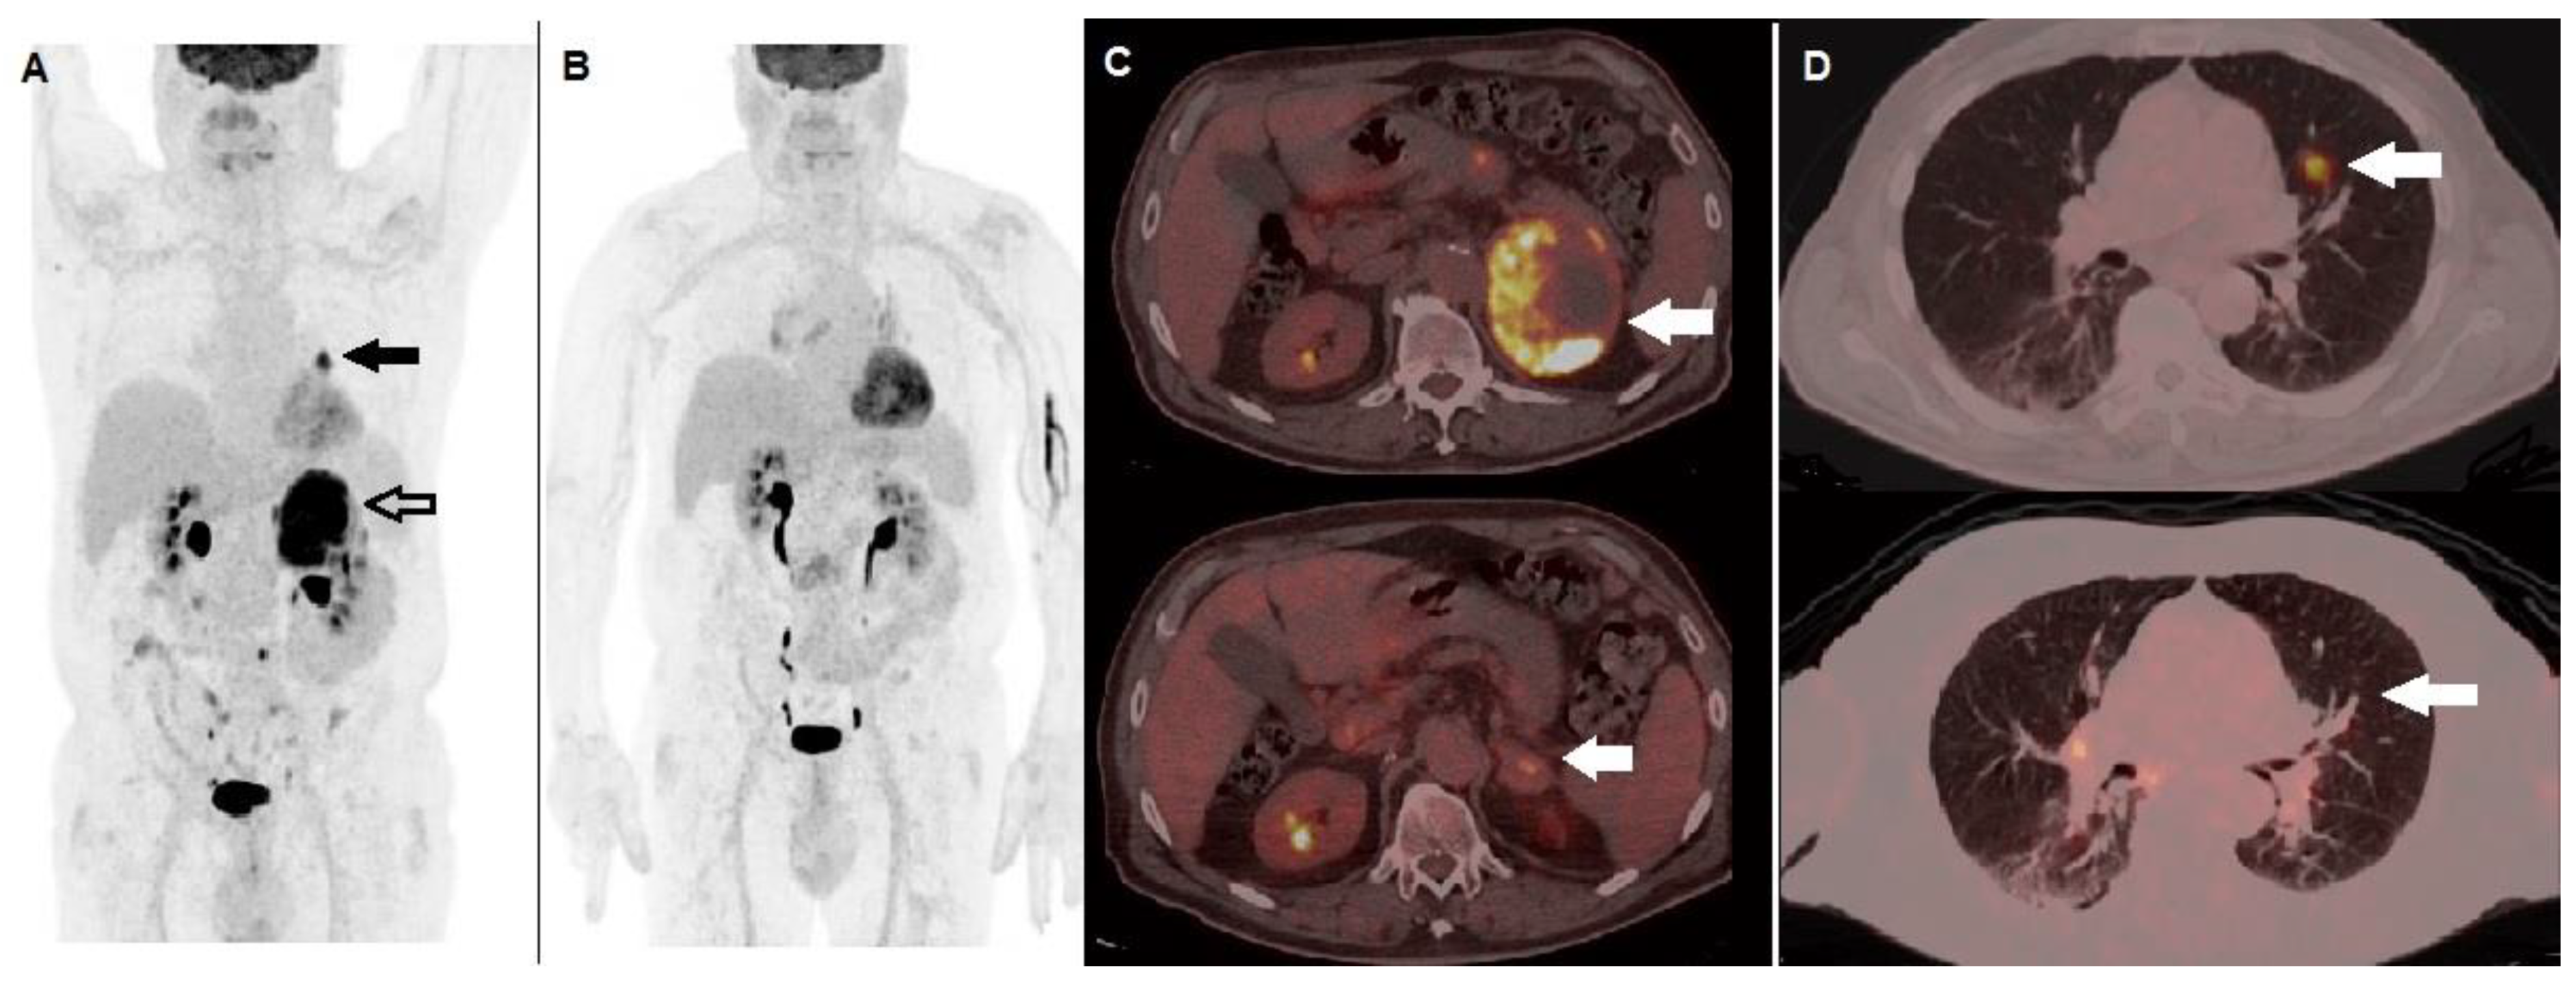

3. 18F-FDG PET/CT for Assessment of Response to Therapy

3.1. Targeted Therapy with BRAF-Inhibitors

- Annovazzi, A.; Ferraresi, V.; Rea, S.; Russillo, M.; Renna, D.; Carpano, S.; Sciuto, R. Prognostic Value of Total Metabolic Tumour Volume and Therapy-Response Assessment by [18F]FDG PET/CT in Patients with Metastatic Melanoma Treated with BRAF/MEK Inhibitors. Eur. Radiol. 2021. head of print. [Google Scholar] [CrossRef]